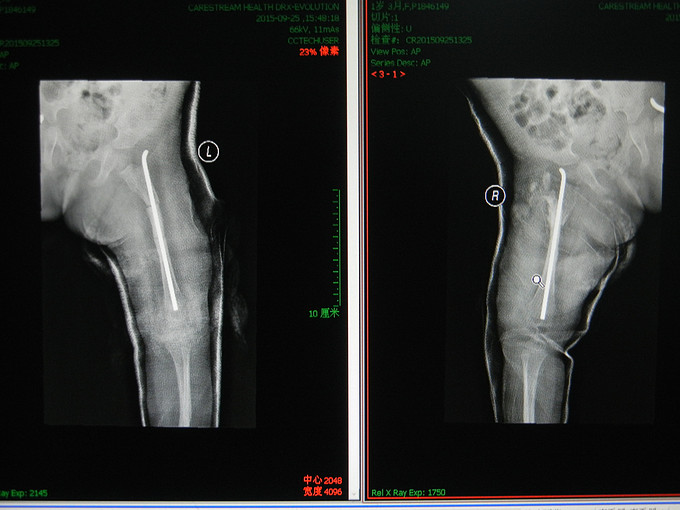

诊断:右股骨骨折,成骨不全。 行手术治疗。

随访:复查X线,术后恢复可。